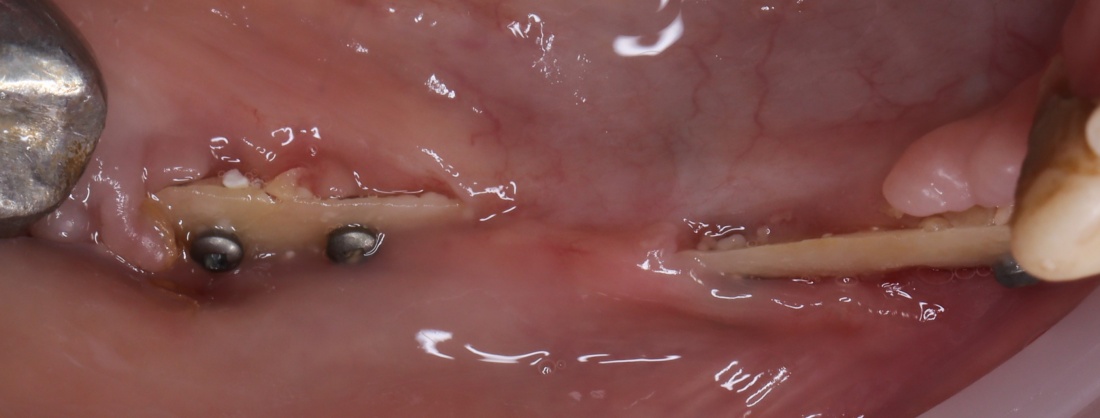

Вот клиническая картина через 4 месяца после ранее проведенной имплантации с остеопластикой:

Как видишь, коллеги из недалекой дружественной страны не осилили снятие швов. Мне это не нравится, хотя и объясняет, почему люди готовы ехать за тыщи километров ради 20-минутной операции удаления зуба мудрости.

Ну хорошо. Швы сняли. Делаем разрез. Обрати внимание, что после всех проведенных операций у нас остается очень небольшой по ширине слой жевательной слизистой оболочки:

Устанавливаем формирователи десневой манжеты. Сегодня я называю эту процедуру не менее важной, чем любой другой этап имплантологического лечения:

И швы. Просто швы. Никаких дополнительных процедур.

Если честно, то сейчас бы я использовал другой шовный материал и другой тип швов. Одно неизменно, — и я об этом много раз говорил, — самая широкая часть формирователя десны должна находиться на уровне десны. Так, чтобы эффективно отрабатывать т. н. «биологическую ширину».